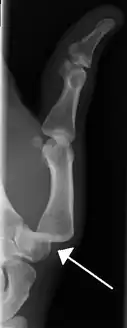

Radiograph of right fifth phalanx dislocation resulting from bicycle accident- Right fifth phalanx dislocation resulting from bicycle accident